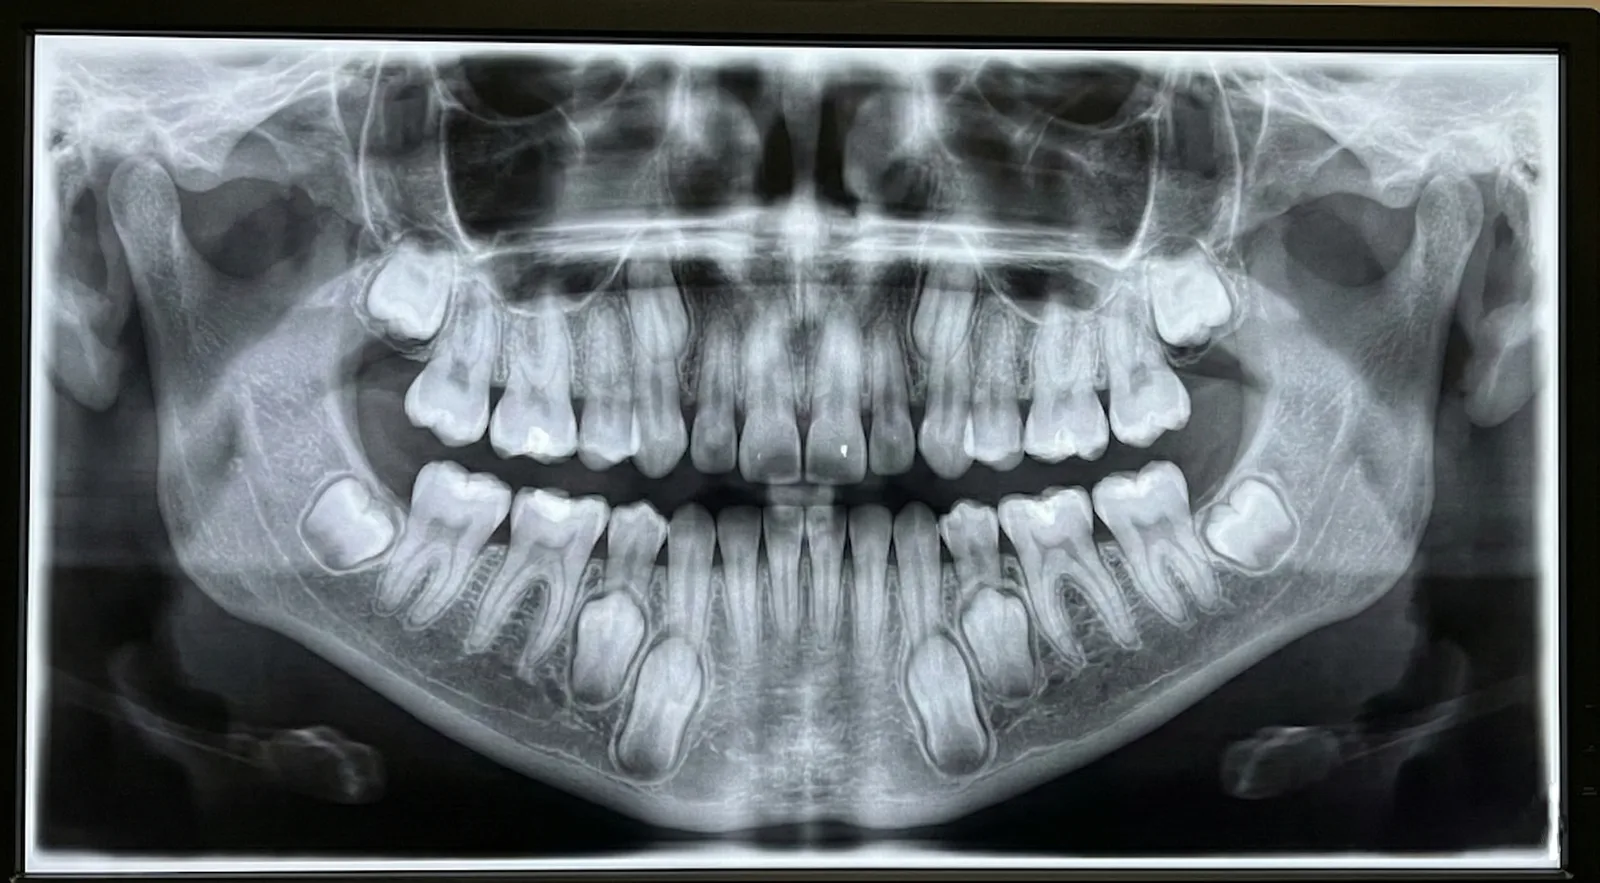

유치 상태, 영구치와의 교환 상태, 교합 변화 등을 성장 단계에 맞춰 평가하고 필요한 관리 방법을 안내합니다.